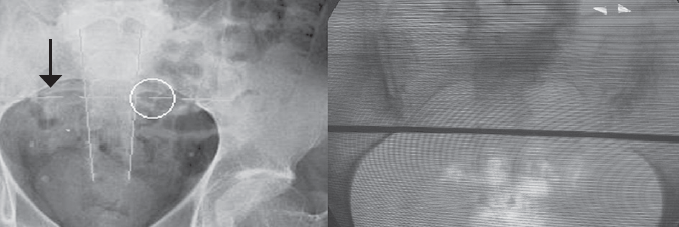

The pudendal nerve trunk is short, and it enters the pelvic area from the sub-piriform space and then passes through the pudendal canal, at the exit of which it branches. Thus, the main place where the nerve trunk can be influenced corresponds to its location next to the sciatic spine of the sciatic bone. The marking for electrode implantation in this area was also performed under X-ray control according to the STAR method (spine, tuberosity, acetabulum, and analrim) [9]. Initially, on the implantation side of the electrode, the middle of the acetabulum was determined, which corresponds to point A. A horizontal line was drawn on the skin through point A with a marker. Then, the point T corresponding to the middle of the lower edge of the ischial tuberosity was determined. A vertical line was drawn through the point T perpendicular to the first one. The intersection of these lines (point S) corresponds to the sciatic spine, which is also visible in the oblique image (with an approximately 15–30° angle of inclination), because in a strictly direct projection it is overlapped with the hip joint or branch of the sciatic bone. From point S, a line was drawn to the outer edge of the anal sphincter (point R). After the points T and R were connected, the resulting segment was divided in half. The middle of this segment served as the point for the needle insertion (yellow circle) and the apex of the triangle (point S) was the target for advancing the needle with the electrode (red circle) (Fig. 2).

Fig. 2. Anatomical landmark for implantation of the electrode on the pudendal nerve: Spine (sciatic spine, S), Tuberosity (ischial tuberosity, T), Acetabulum (coxal cavity, A), Analrim (anal sphincter, R) (left) (see explanation in the text). Projection points of the pudendal nerve (red circle) and the location of the skin incision to insert the Tuohi needle (yellow circle) (right)

Рис. 2. Анатомический ориентир для имплантации электрода на половой нерв: Spine (седалищная ость, S), Tuberosity (седалищный бугор, T), Acetabulum (вертлужная впадина, A), Analrim (анальный сфинктер, R) (слева) (см. пояснение в тексте). Разметка маркером точки проекции полового нерва (красный круг) и место разреза кожи для введения иглы Туохи (желтый круг) (справа)